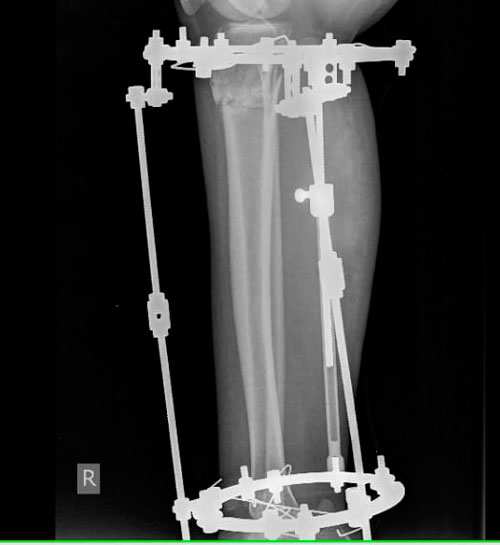

IMG-20181128-WA0023.jpg

IMG-20181128-WA0014-(1).jpg